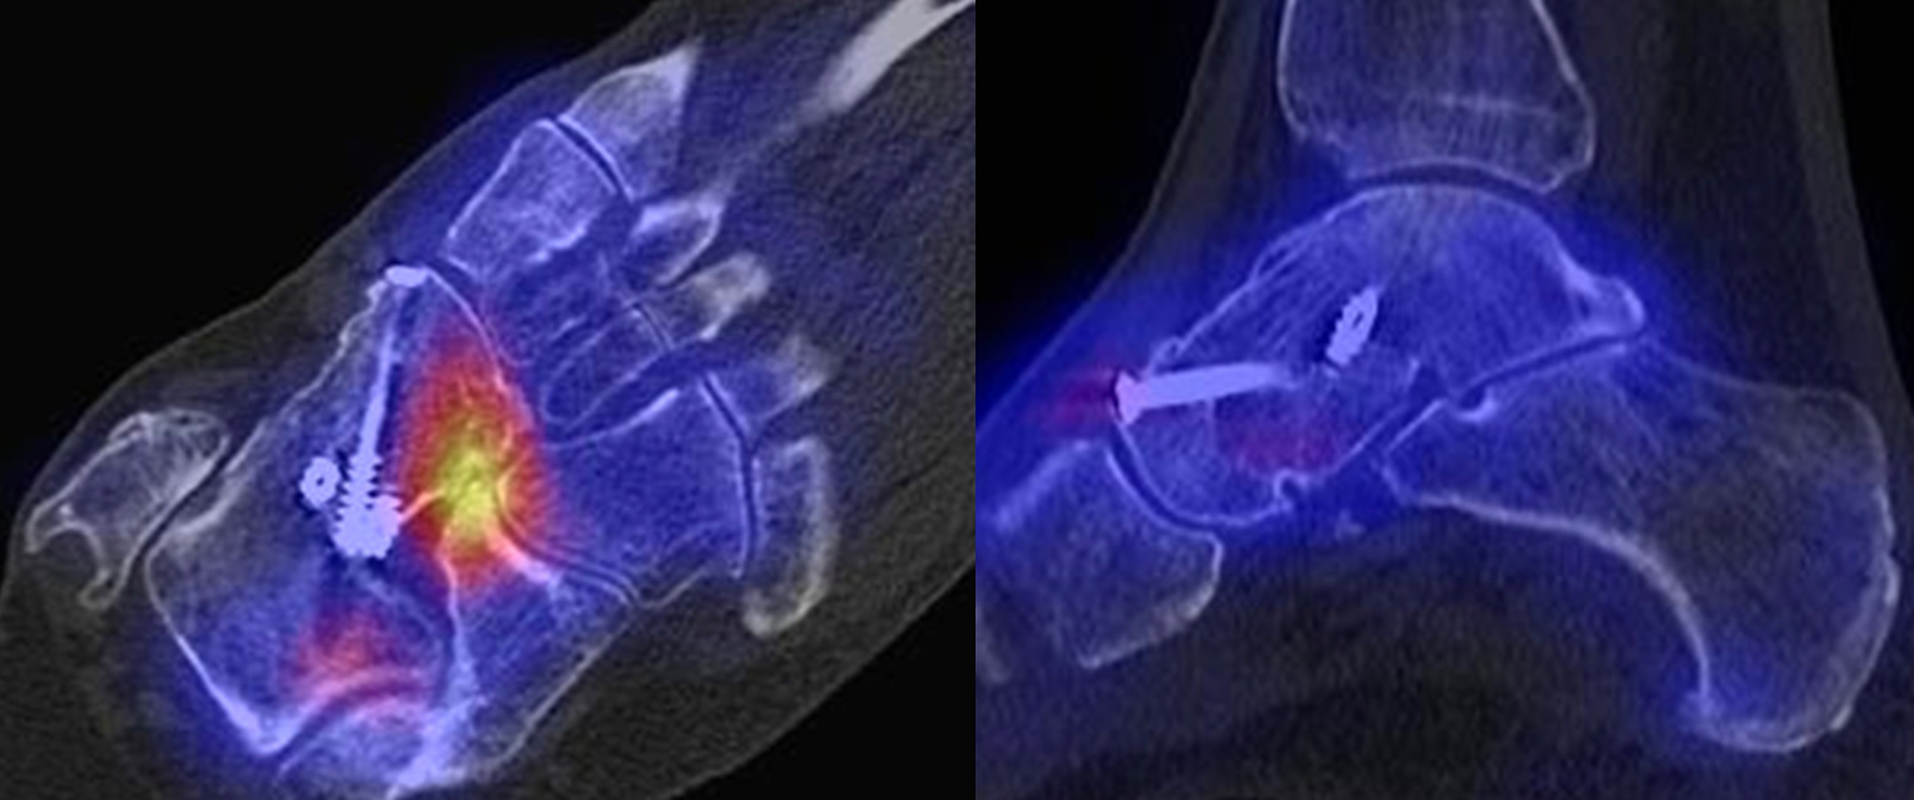

SPECT/CT zur Beurteilung von Arthrodesen

Arthrodesen gehören seit langem zu den Standardverfahren bei Fehlstellungen oder schmerzhaften Arthrosen 4546 (Graves, 2000). Eine zumindest teilweise knöcherne Durchbauung von Arthrodesen sollte in der Regel innerhalb von 6 Monaten nach der OP nachweisbar sein 647. Eine unvollständige oder fehlende Fusion nach Arthrodese kann permanente Schmerzen verursachen, was sich mit der SPECT/CT nachweisen lässt. Abbildung 5.1. zeigt den Fall eines Patienten mit persistierenden Beschwerden 1 Jahr nach calcaneo-cuboidaler Arthrodese, es besteht ein erhöhter Knochenmetabolismus im Bereich der Arthrodese bei teilweise noch abgrenzbarem Gelenkspalt; kein Nachweis von Anschlussarthrosen in den benachbarten Gelenken. Persistierende Beschwerden nach Arthrodese können jedoch auch durch Überlastungen angrenzender Gelenke entstehen, die dann in Arthrosen münden 48. Ein entsprechendes Beispiel ist in Abbildung 5.2. dargestellt, die den Verlauf bei einer Patientin mit Z. n. Arthrodese wegen einer talonavicularen Arthrose zeigen.

Ein weiteres Beispiel für eine im Verlauf entstandene symptomatische Arthrose in den Nachbargelenken zeigen die Abbildungen 5.3.a und b. Bei dem Patienten bestand ein Z. n. subtalarer und talo-navikularer Arthrodese vor 11 Monaten mit Beschwerden beim Abrollen im linken Sprunggelenk mit dem Gefühl „einer Sperre“. Abbildung 5.3.b zeigt die Entwicklung einer anterior betonten hypermetabolen OSG-Arthrose mit Zeichen einer teilweise knöchernen Durchbauung der subtalaren Arthrodese links. Noch keine signifikante Durchbauung der talo-navikularen Arthrodese links. Die Abbildungen 5.4.a bis c zeigen als Erklärung für Schmerzen eine symptomatische Osteochondrale Läsion in der Talusrolle bei knöcherner und reizloser Durchbauung der Arthrodesen 14 Monate nach USG- und TN-Arthrodese.

Beispiele für SPECT/CT-Untersuchungen nach OSG-TEP sind in den Abbildungen 6.1. bis 6.3. abgebildet.